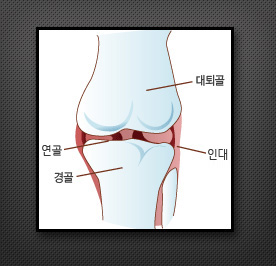

인공 슬(무릎)관절 치환술이란

각종관절염(퇴행성, 류마티스성, 외상성)이 심한 경우 무릎관절이 극심한 통증, 변형으로 인해 정상적인 보행을 할 수 없게 됩니다.이 경우 손상된 무릎관절 연골뼈를 제거하고 그 부위에 특수합금과 고분자 플라스틱 재질로 된 인공관절을 삽입하여 통증을 감소시키고 변형을 교정하는 시술을 인공 슬(무릎)관절 치환술이라 합니다.